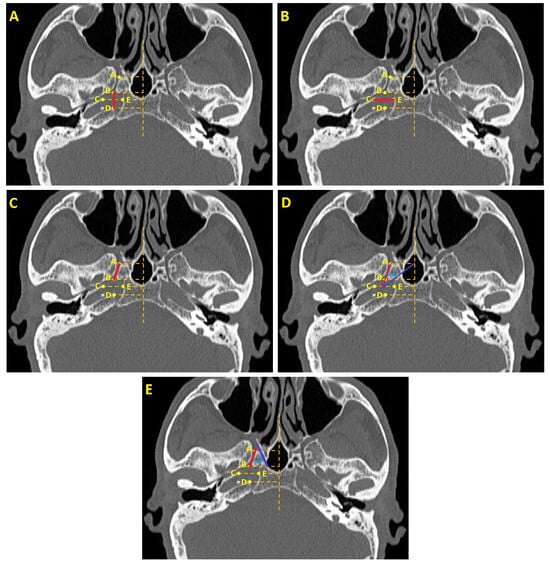

| Parameters | Definitions of Landmarks (Figure 1) |

|---|---|

| FL length(mm) | The distance between the posterior end of the VC opening into the FL and the petrous apex of the temporal bone (B–D). |

| FL width (mm) | The distance between the temporal bone’s petrous apex and the sphenoid bone’s corpus (C–E). |

| VC length (mm) | The distance between the anterior end of the VC opening into the pterygopalatine fossa and the posterior end of the VC opening into the FL (A,B). |

| VC—pterygosphenoidal fissure angle (°) | The angle formed between the VC and the oblique line drawn from the pterygosphenoidal fissure. |

| VC—palatovaginal canal angle (°) | The angle formed between the VC and the oblique line drawn from the palatovaginal canal. |